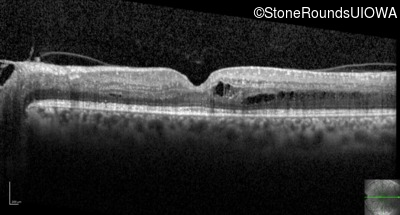

Optical Coherence Tomography - Right - Count Fingers 1'

Exemplar / OCT Stack

OCT Stack